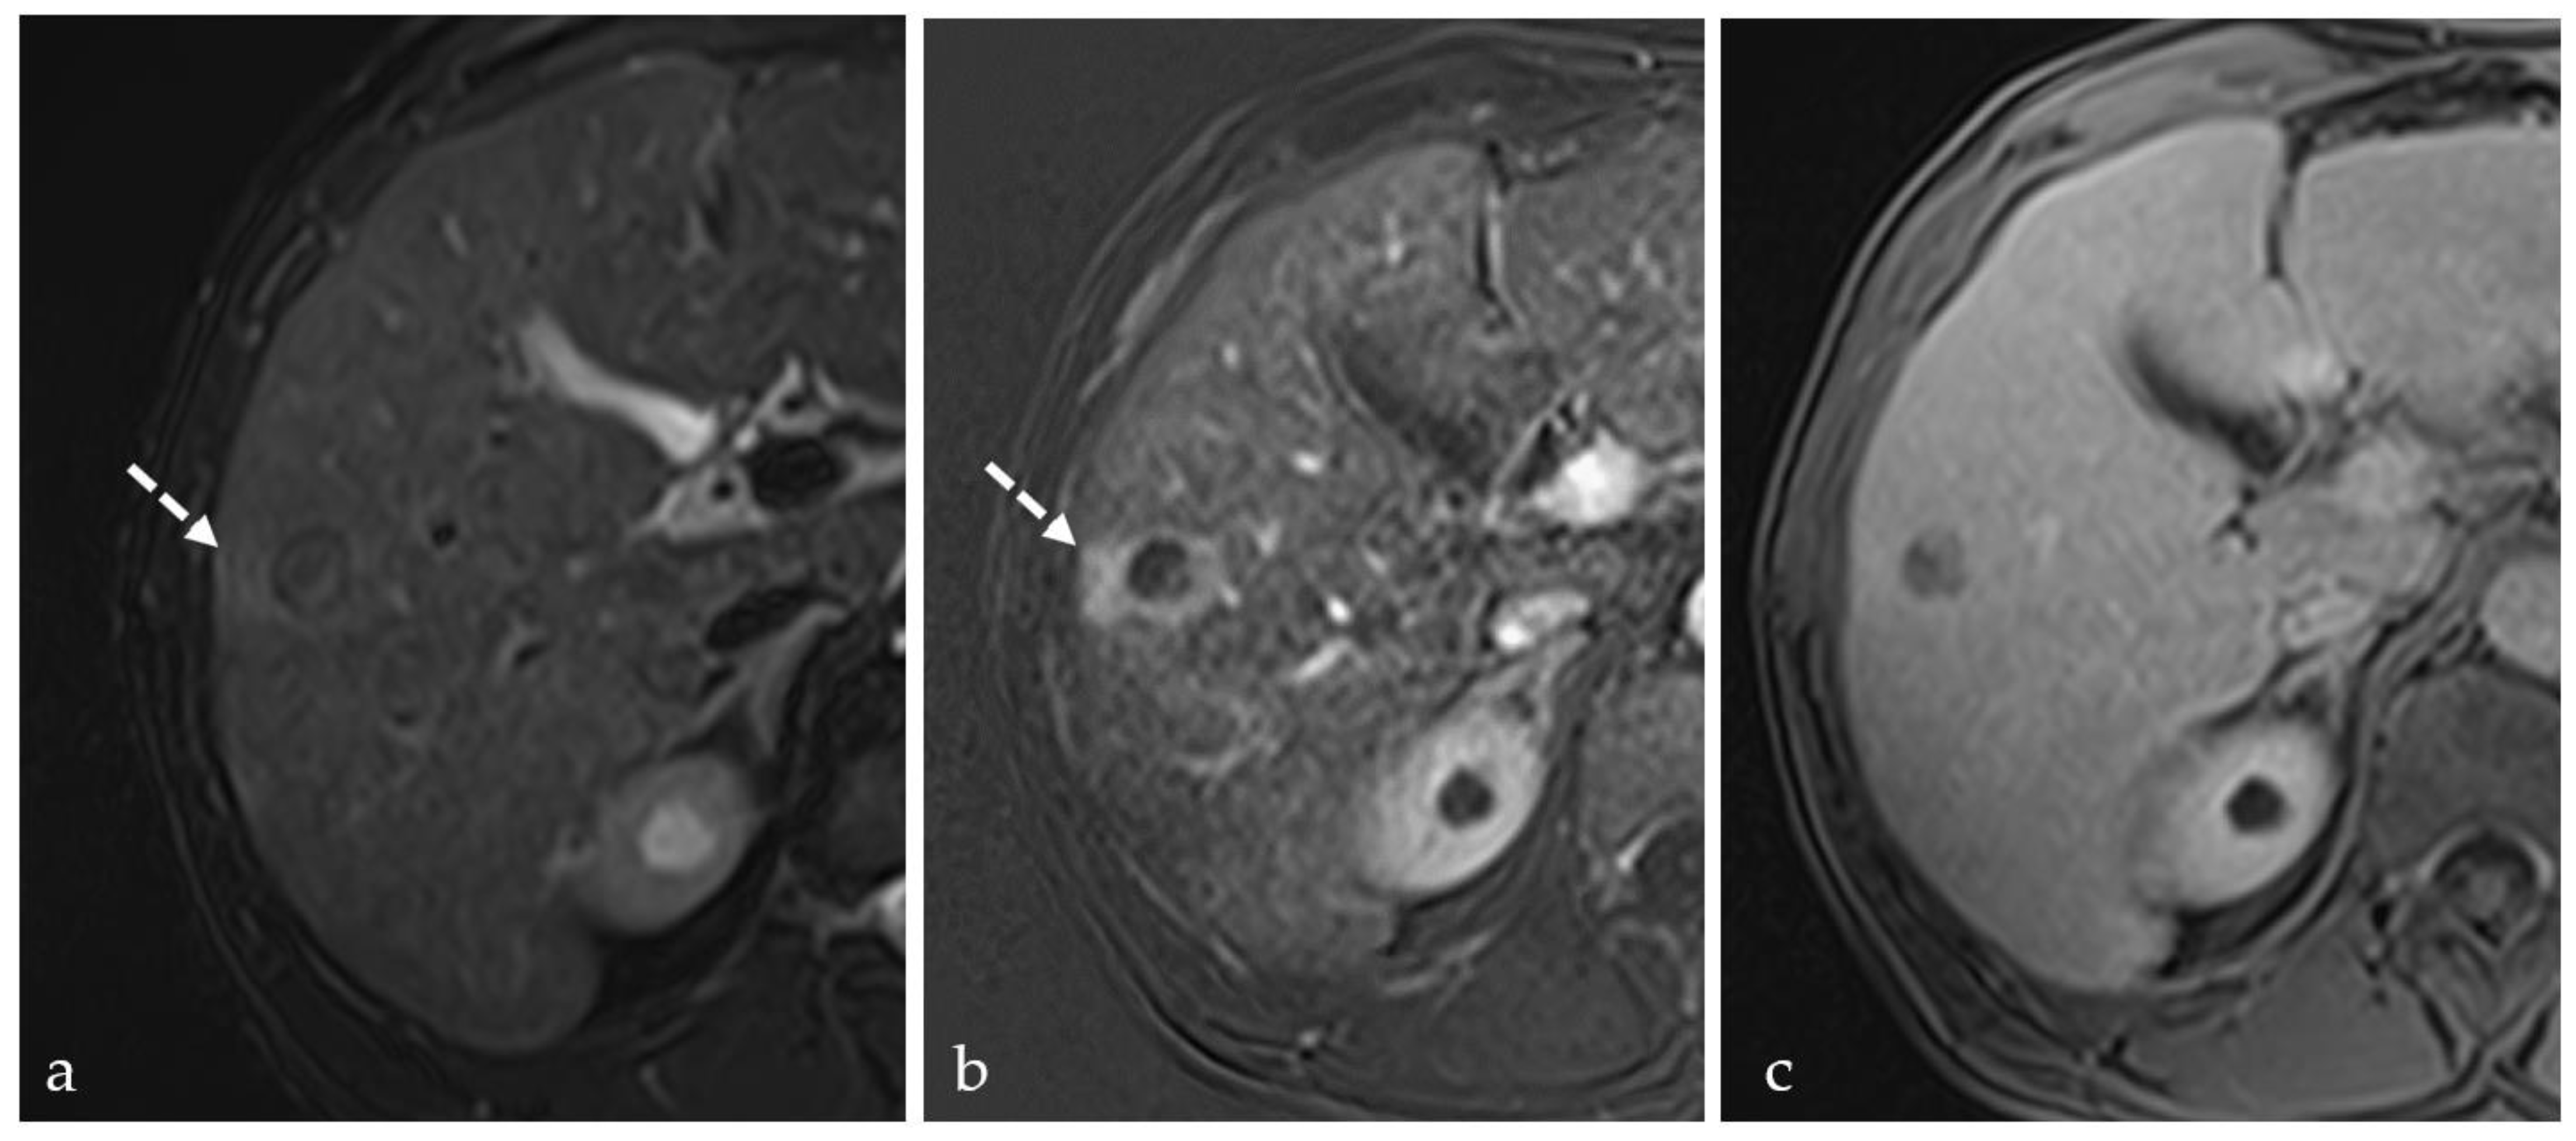

3.2. Expected Post-Treatment Imaging Features in the Absence of Viable Tumor Tissue

3.5. Post-Treatment Imaging Features of Tumor Viability